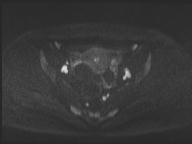

轴位

DWI

此外,肿瘤还累及宫旁组织。影像学检查发现异常淋巴结肿大,最大短轴直径(SAD)为10 mm,位于髂总血管分叉处和髂内动脉链下方。该淋巴结肿大在弥散加权成像(DWI)上显示水限制,且增强扫描后可见强化。